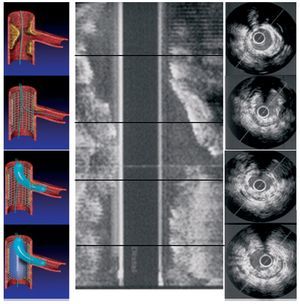

Se realizó un estudio prospectivo observacional en 23 pacientes consecutivos con lesiones coronarias que afectaban a una bifurcación, excluidos los casos en que el vaso secundario tuviera un diámetro < 2,5 mm. Los datos clínicos basales se resumen en la tabla 1. En su mayoría eran varones hipertensos y fumadores, y más de la mitad de los pacientes se presentaron en situación inestable. En cuanto a las características angiográficas basales (tabla 2), cabe destacar que el 35% de las lesiones eran calcificadas, y la localización más frecuente fue a nivel de la descendente anterior con la diagonal. Se utilizó la clasificación de Medina12 para definir el compromiso de los distintos segmentos de la bifurcación. En 14 (60%) pacientes estaban afectados los tres segmentos de la bifurcación y en 5 (24%) el RS quedó afectado tras implantar el stent en el VP. Todos los stents fueron liberadores de fármacos. La ecografía intracoronaria (IVUS) (Atlantis SR, Boston Scientific 2.5 F, 40 MHz) se realizó tras la administración de un bolo de 200 mg de nitroglicerina, con una retirada motorizada a 0,5 mm/s. En 12 (52%) pacientes se realizó un IVUS basal. En todos los casos se hizo estudio ultrasónico tras implantar el stent en el VP, tras dilatar con balón el RS y tras el inflado simultáneo con dos balones superpuestos en KB. El balón que se utilizó para dilatar el RS se escogió en función del diámetro del vaso, y se infló a 6-8 AT, sin observar en ningún caso muesca residual. Para la dilatación en kissing, se utilizó en el VP el balón del stent u otro de diámetro similar, alcanzándose presiones de inflado de 12-14 AT, y para el RS, se utilizó el balón usado previamente para la dilatación aislada del mismo, con presiones de inflado entre 6 y 8 AT. En cada una de las condiciones se realizaron medidas del área del stent y del índice de simetría (diámetro menor del stent / diámetro mayor del stent) en el segmento proximal del stent, a nivel de la salida del RS, en el segmento inmediato a la salida del RS y en el segmento distal del stent, pudiendo evaluar tanto la ganancia o la pérdida del área como los cambios producidos en la geometría del stent tras cada maniobra realizada (fig. 1). También se midió el ángulo entre el RS y el VP, y se correlacionó con el grado de deformidad producido en el bajo rombo tras dilatar aisladamente el RS. Las mediciones fueron realizadas off-line por dos cardiólogos intervencionistas expertos.

Fig. 1. Protocolo del estudio ultrasónico. A la izquierda se muestra cada una de las condiciones en las que se realiza el IVUS, y a la derecha los segmentos del stent estudiado en cada condición.